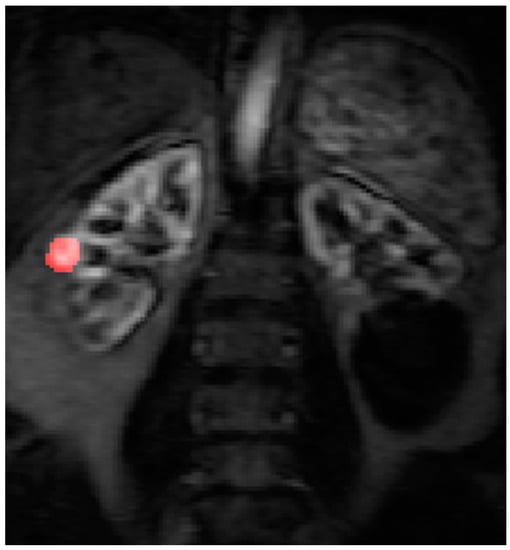

2.4. Data Post Processing

All the MR images were anonymized and post processing was performed offline by a single consultant radiologist with greater than 10 years of clinical experience (Dr Tze Min Wah). Images were uploaded into PMI 0.4 (Platform for Research in Medical Imaging Version 0.4 [13], which was running on a desktop PC. A standardized 4-voxel region was used to extract an arterial input function (AIF). This region of interest (ROI) was drawn inside the aorta at the approximate level of the origin of the vascular pedicles of the kidneys (Figure 1 and Figure 2).

Figure 1. The arterial input function (AIF) region of interest (ROI) was drawn inside the aorta at the approximate level of the origin of the vascular pedicles of the kidneys in the dynamic series.